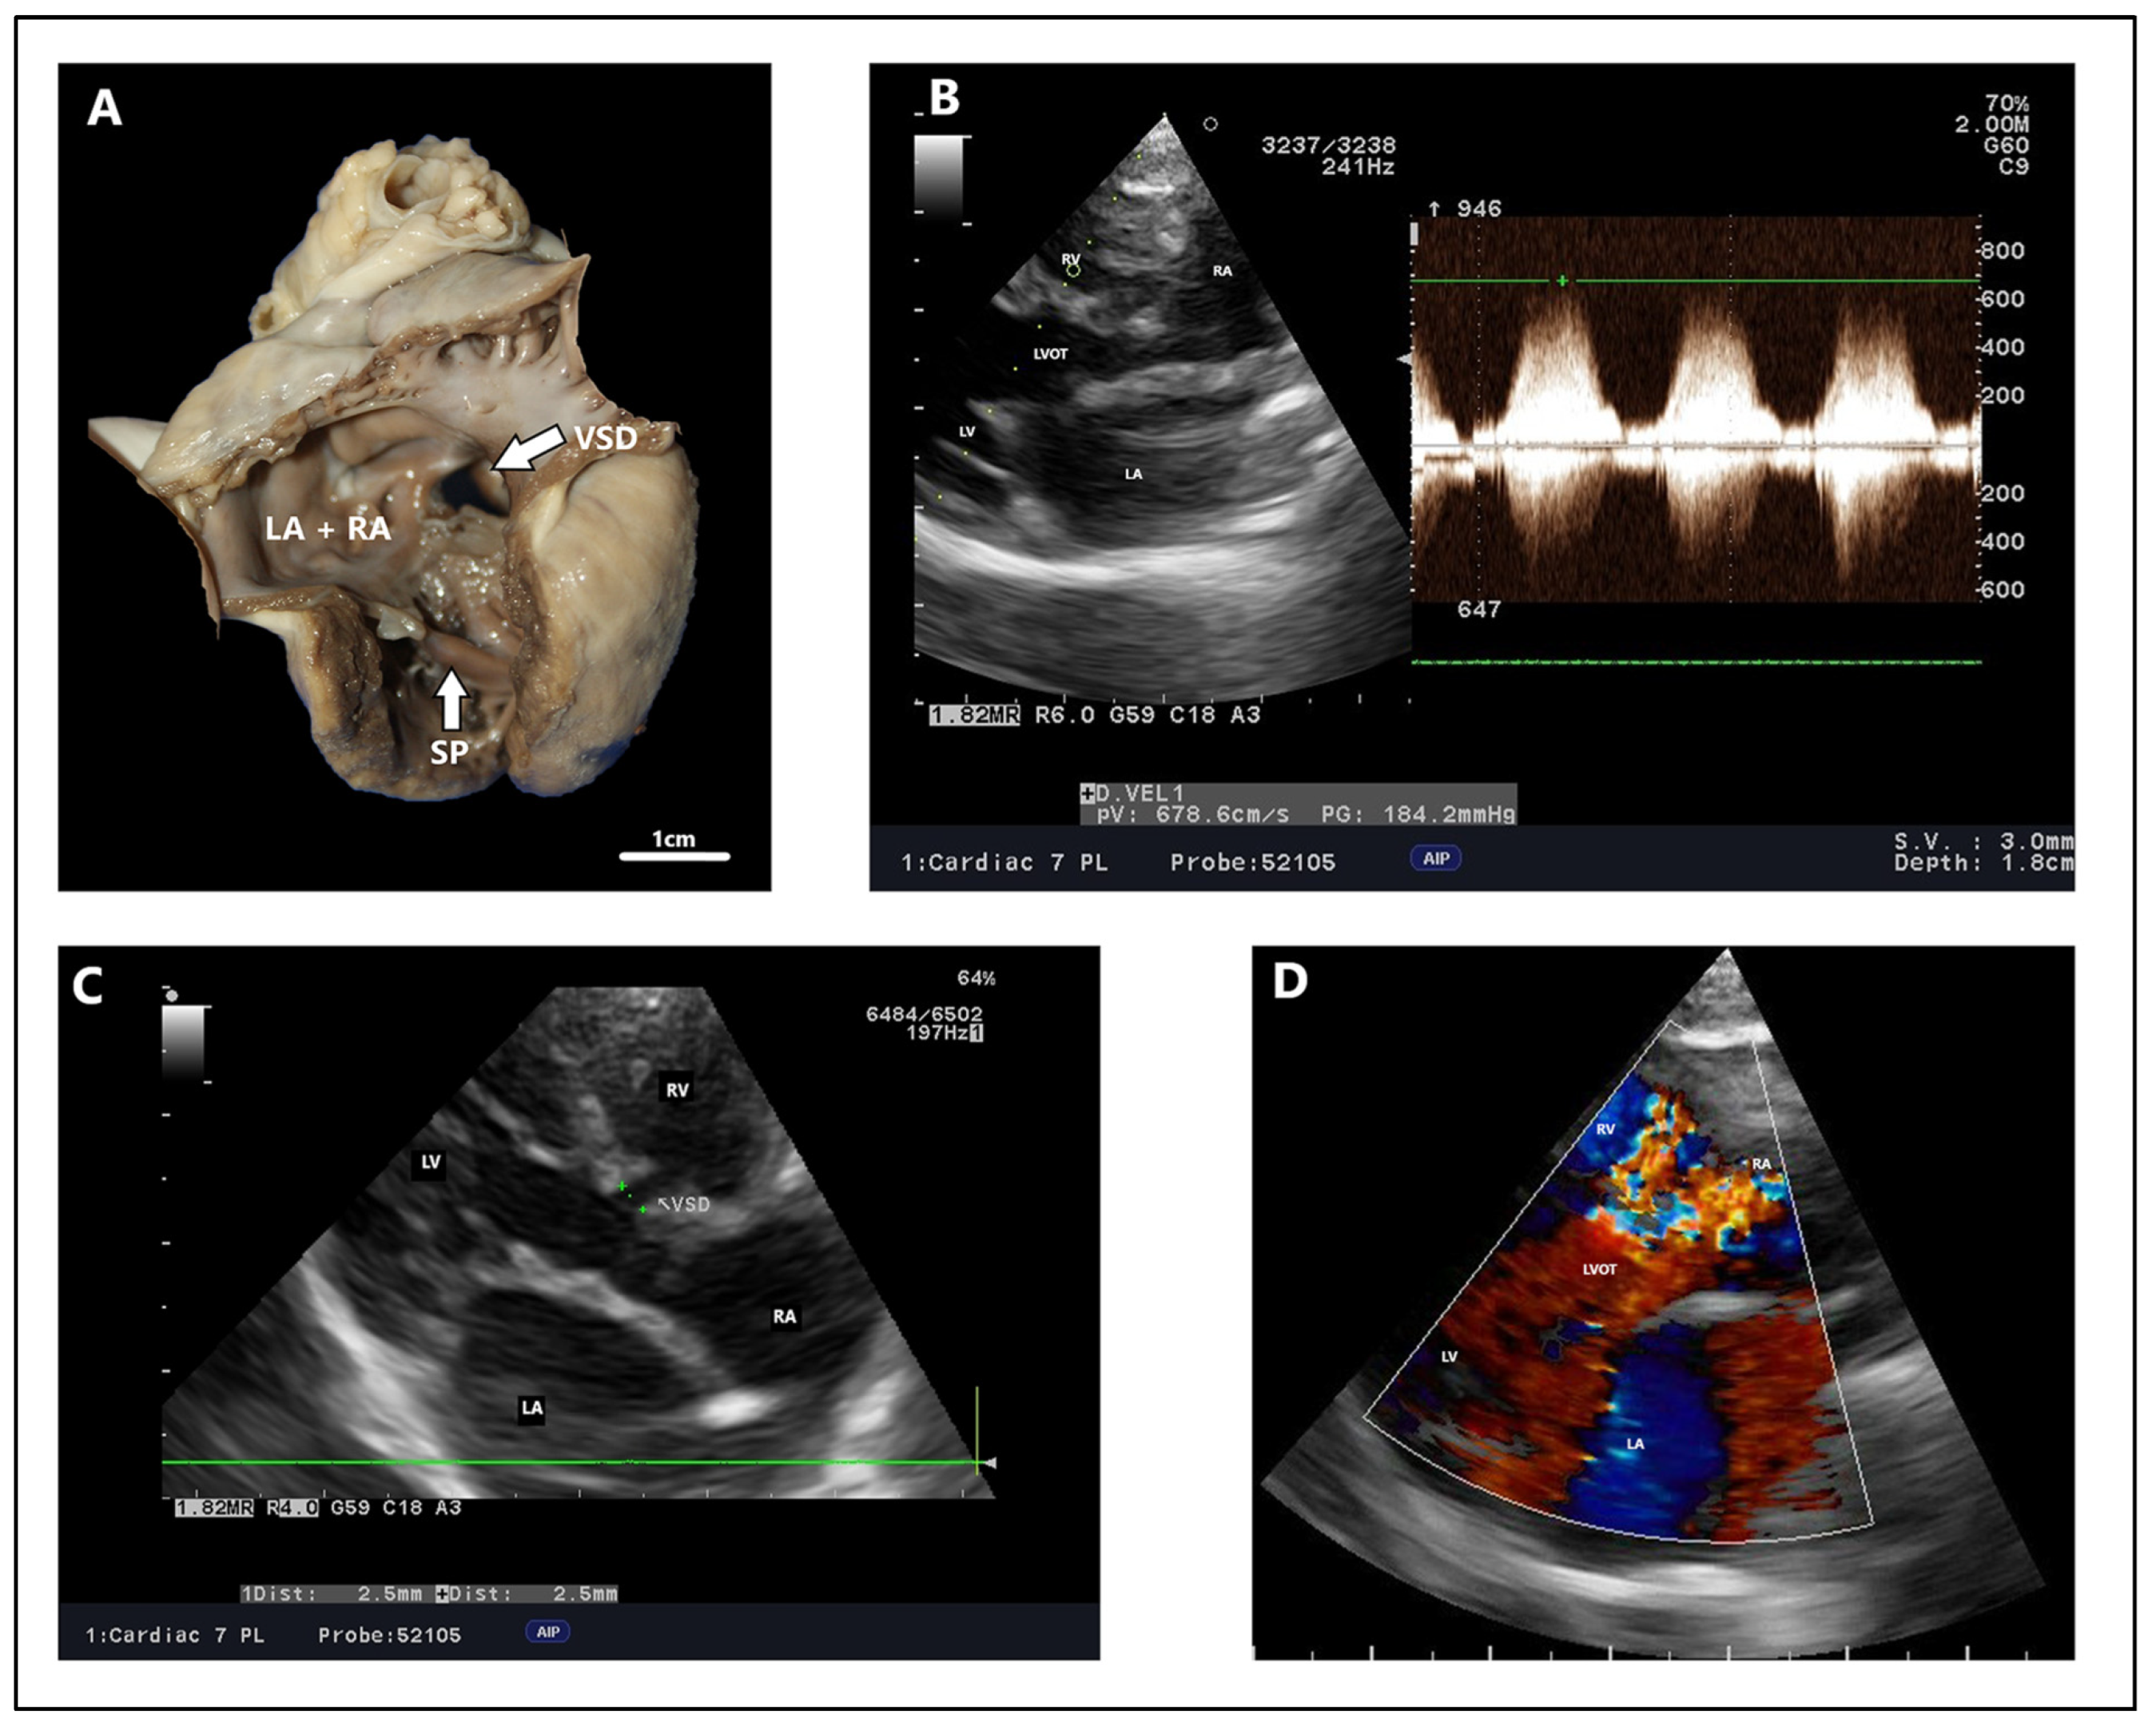

Atrioventricular septal defect with ventricular communication (inflow ventricular septal defect), domestic short-hair cat, four months. (A) Necropsy at six months due to congestive heart failure, with inflow ventricular septal defect visible on the dissected heart. (B) Spectral Doppler, maximum velocity peak of ventricular septal defect, modified right parasternal five-chamber view to estimate the maximum velocity peak. (C) Modified right parasternal five-chamber view to obtain the best estimation of the diameter of the defect. (D)—Color Doppler, characteristic “butterfly pattern” of atrioventricular septal defect with ventricular communication in the right four-chamber longitudinal axis. Multicolor in the upper part of the image indicates turbulent, rapid blood flow. LA: left atrium. LV: left ventricle. RA: right atrium. RVOT: right ventricular outflow tract. RV: right ventricle. SP: septal band. VSD: ventricular septal defect.

Figure 5.